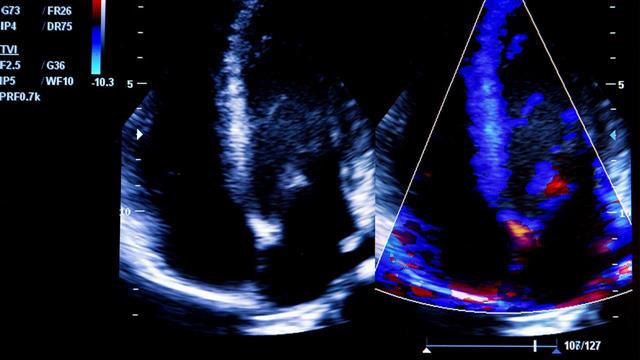

Συνολικά, καρδιαγγειακές και νεφρικές επιπλοκές εμφανίστηκαν σε 10.421 (28,7%) ασθενείς. Παρατηρήθηκε μια μη γραμμική συσχέτιση μεταξύ του επιπέδου γλυκόζης εισαγωγής και των καρδιαγγειακών και νεφρικών επιπλοκών. Ωστόσο, οι ερευνητές διαπίστωσαν ότι η φύση της μη γραμμικής σχέσης ήταν συγκεκριμένη ανάλογα με το αποτέλεσμα.

• Μεγαλύτερη πιθανότητα εμφάνισης καρδιακής ανεπάρκειας, αρρυθμίας και επιπλοκών πήξης συσχετίστηκε με επίπεδα γλυκόζης στο υπογλυκαιμικό εύρος.

• Η συσχέτιση μεταξύ του επιπέδου γλυκόζης και των πιθανοτήτων εμφάνισης καρδιακής ανακοπής, καρδιακής ισχαιμίας και εγκεφαλικού επεισοδίου χαρακτηρίστηκε από αυξανόμενες πιθανότητες με αυξανόμενα επίπεδα γλυκόζης εισαγωγής.

• Για την καρδιακή ισχαιμία και το εγκεφαλικό επεισόδιο η αύξηση των πιθανοτήτων ήταν γραμμική σε όλη την κατανομή της γλυκόζης.

• Για την καρδιακή ανακοπή, ο ρυθμός αύξησης μειώθηκε σε υψηλότερες τιμές γλυκόζης.